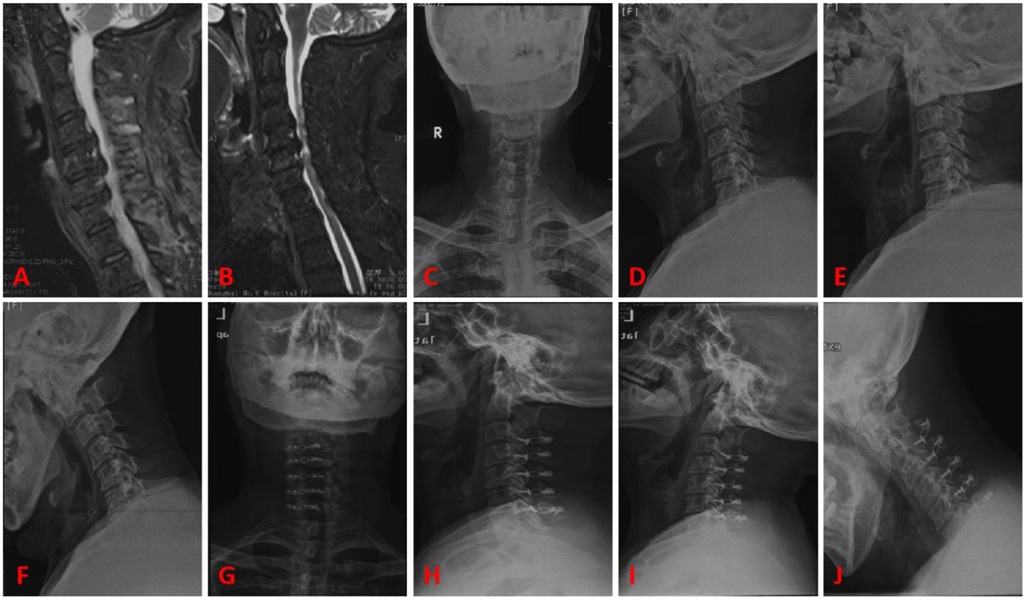

3.6 Typical cases

Case 1, female patient, 50 years old. A, B are preoperative sagittal MRI images, showing varying degrees of disc protrusion at the C4/5, C5/6, and C6/7 levels. C, D are preoperative anterior-posterior x-rays, showing loss of cervical lordosis. E, F are preoperative flexion-extension x-rays, showing instability of the C2 vertebra. G, H are postoperative follow-up lateral x-rays, showing good position of the internal fixation. I, J are postoperative follow-up flexion-extension x-rays, showing no significant changes in the instability of the C2 vertebra. See Figure 4.

Figure 4

MRI and X-ray images of the cervical spine in sagittal and frontal views. Images A and B show sagittal MRI scans depicting the spine structure. Images C to J display X-ray images from various angles and views, highlighting cervical vertebrae alignment and potential abnormalities. Each is labeled from A to J in red.

Figure 4. Typical case 1. (A,B) Preoperative sagittal MRI images, showing varying degrees of disc protrusion at the C4/5, C5/6, and C6/7 levels. (C,D) Preoperative anterior-posterior x-rays, showing loss of cervical lordosis. (E,F) Preoperative flexion-extension x-rays, showing instability of the C2 vertebra. (G,H) Postoperative follow-up lateral x-rays, showing good position of the internal fixation. (I,J) Postoperative follow-up flexion-extension x-rays, showing no significant changes in the instability of the C2 vertebra.